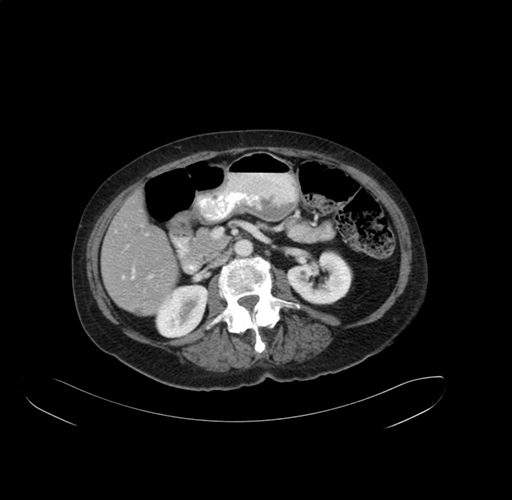

Axial Venous

Coronal Venous